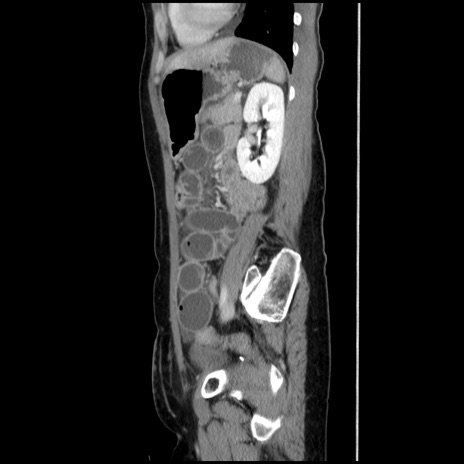

症例32(矢状断像)

【症例】40歳代 女性

【主訴】上腹部痛、嘔気・嘔吐

【現病歴】約9時間前頃から急に上腹部痛、嘔気、嘔吐が出現。改善しないため救急要請。

【既往歴】子宮頚癌(広汎子宮全摘術、放射線療法)、腸閉塞

【身体所見】腹部:平坦、軟、腸雑音亢進、上腹部を中心に腹部全体に圧痛あり。

【データ】WBC 8400、CRP 0.03